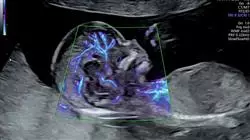

Tauchen Sie ein in die Welt der Krankenpflege mit dem Universitätskurs in Geburtshilfliche Notfälle im Zweiten und Dritten Trimester für Hebammen, eine einzigartige Gelegenheit, die Ihnen die TECH Technologische Universität bietet. Sind Sie bereit, Ihre Kenntnisse und Fähigkeiten auf dem Gebiet der Geburtshilfe zu erweitern? Unser Online-Programm nimmt Sie mit auf eine Entdeckungsreise, auf der Sie die Komplexität geburtshilflicher Notfälle zu kritischen Zeiten im zweiten und dritten Trimester erkunden werden. Unser Dozententeam, das sich aus renommierten Fachleuten auf diesem Gebiet zusammensetzt, wird Sie durch klinische Fälle, aktuelle Protokolle und strenge Analysen führen. Sie werden lernen, schwierige Situationen mit Ruhe und Präzision zu meistern und die entscheidenden Fähigkeiten zu entwickeln, um in einem Umfeld mit hohem Druck eine qualitativ hochwertige Versorgung zu gewährleisten. Von der frühzeitigen Erkennung von Komplikationen bis hin zu fundierten Entscheidungen - dieser Kurs wird Ihnen das nötige Rüstzeug für eine hervorragende Geburtshilfe vermitteln. Sie werden sich mit Themen wie Schwangerschaftsbluthochdruck, Blutungsmanagement und medizinischen Notfällen während der Geburt befassen.